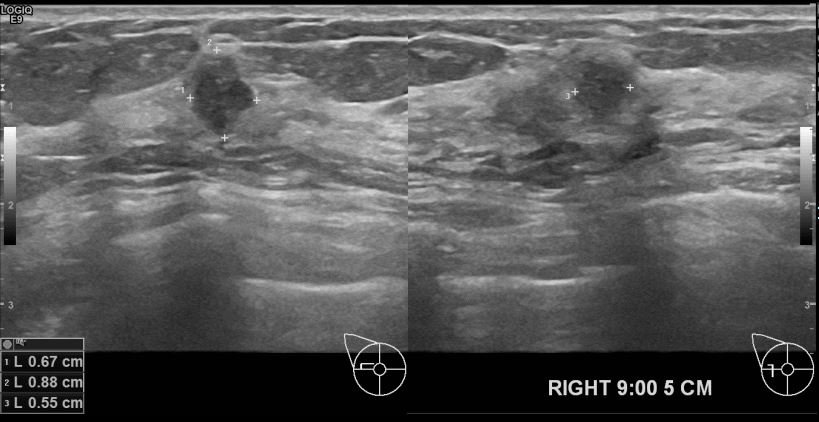

상기환자 외부검사상 이상소견으로 내원하신 60대 여성분으로 우측유방의 조직검사시행후

유방암 진단되셨읍니다.빠른 쾌유 바랍니다.